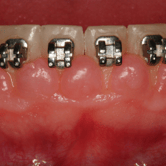

Hiperplasia gingival

La hiperplasia gingival es el aumento del tamaño de las encías debido a la proliferación de tejido gingival.

Los pacientes notan que sus encías están muy grandes y cubren parte de sus dientes. Esto puede dificultar la limpieza y aumentar el riesgo de infecciones.

El tratamiento inicia con una limpieza profunda, mejorar cepillado y puede incluir cirugía para reducir el exceso de tejido (gingivectomia)